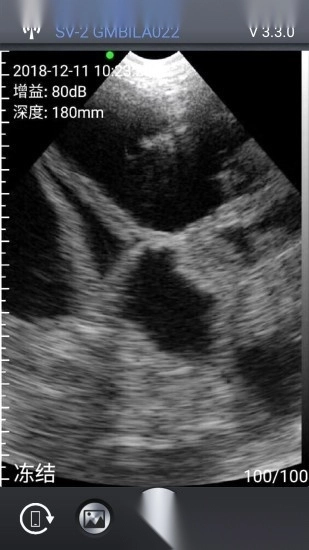

该应用可与指定品牌的无线兽用B超仪快速建立连接,随后在软件内清晰呈现诊断细节与结果。它致力于为养殖工作者提供优质服务,使得掌握猪群健康状况变得简单快捷。应用安装后,成功配对硬件设备即可开始检测,流程顺畅高效。软件还集成了多项实用功能,满足日常养殖的多种需求。

3、通过专用无线网络即可完成连接,并在应用中观察图像;